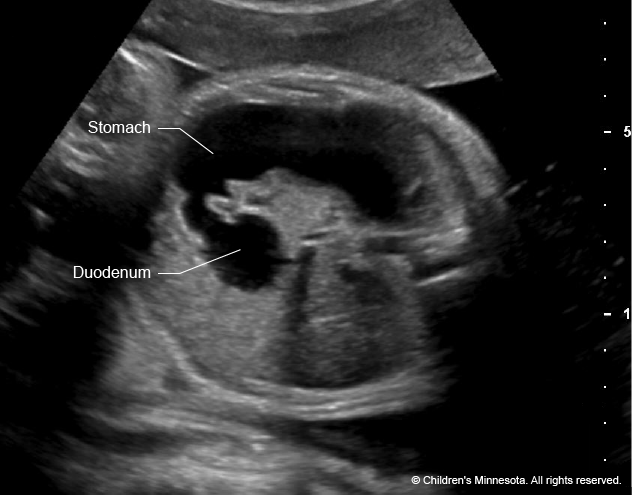

AXR: dilated loops of bowel proximal to atresia + classic double bubble (can also be seen on USS)

Double bubble occurs because there is dilation of the stomach and proximal duodenum due to atresia